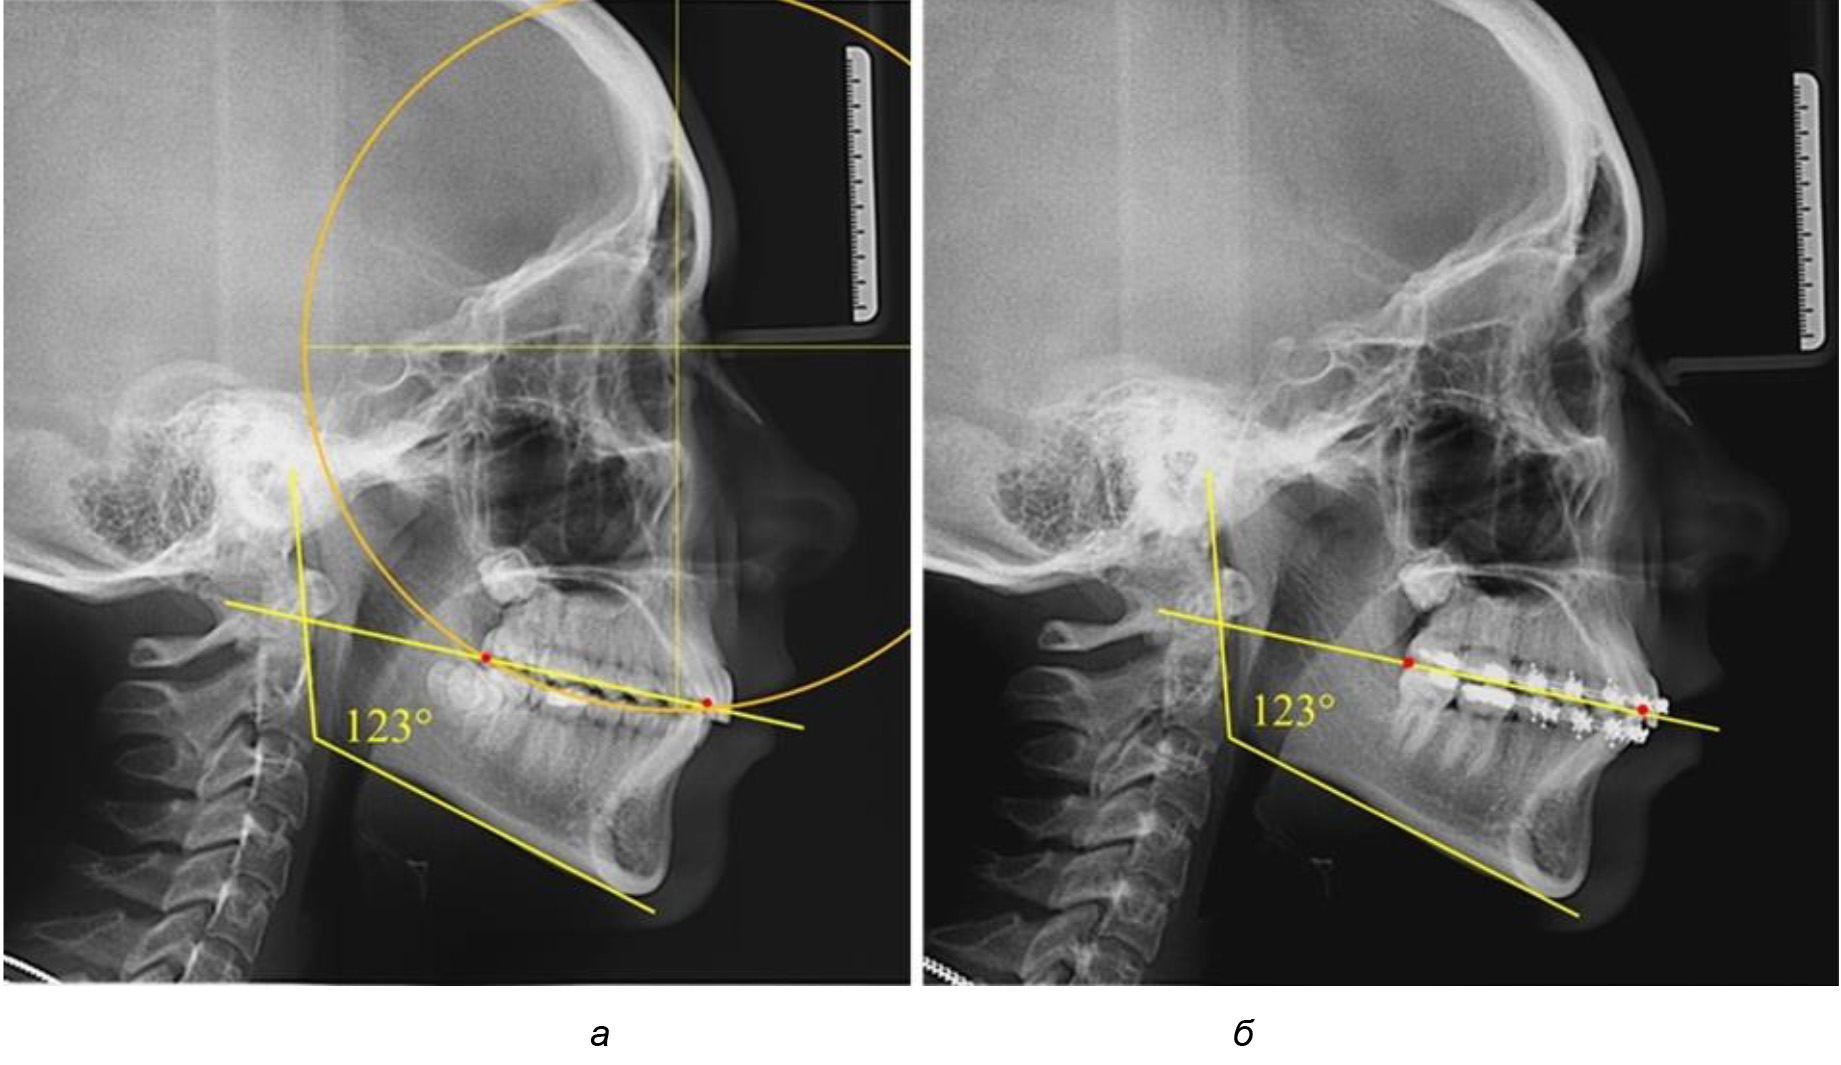

У людей с аномалиями окклюзии по сагиттали в 1-й подгруппе обследовано 9 человек. Обращает на себя внимание увеличение глубины кривой Spee, что нами расценивалось, как патологическая форма кривой линии окклюзии.

Глубина кривой Spee в среднем по 2-й подгруппе составила (5,69 ± 1,57) мм, что было достоверно больше, чем у людей с физиологической окклюзией (р ˂ 0,05). Достоверных различий с показателями, полученными при анализе ТРГ и ОПТГ, нами не отмечено (р ˃ 0,05). Отношение радиуса окружности к сагиттальному размеру окклюзионной линии в среднем по подгруппе составляло 1,372 ± 0,042 и не соответствовало числу Фибоначчи, что может быть использовано в качестве диагностического критерия определения патологической формы кривой Spee. После лечения пациентов техникой «прямой» дуги было отмечено незначительное увеличение сагиттального размера окклюзионной лини в среднем на (2,12 ± 0,77) мм. Однако окклюзионная линия практически касалась окклюзионного контура всех жевательных зубов, и отмечалось практически полное отсутствие кривой Spee.

Таким образом, проведенное лечение техникой «прямой» дуги способствует нормализации окклюзионного равновесия и торку передних зубов, однако не соответствует оптимальному окклюзионному статусу, характеризующему физиологическую окклюзию. При этом величина нижнечелюстного угла оставалась на прежнем уровне (рис. 5).

Рис. 5. Особенности ТРГ при патологической кривой Spee до лечения (а) и после лечения (б) техникой «прямой» дуги

Во 2-й подгруппе 2-й группы было обследовано 7 человек.

Указанная величина не имела достоверного отличия с 1-й подгруппой (р ˃ 0,05), что определяло однородность групп по количественному признаку.

Обращает на себя внимание, что глубина кривой Spee в анализируемой подгруппе практически не отличалась от показателей, полученных у людей с физиологической окклюзией, и составляла (4,23 ± 1,58) мм. Отношение радиуса окружности к сагиттальному размеру окклюзионной линии в среднем по подгруппе составляло 1,623 ± 0,02 и соответствовало числу Фибоначчи.

После лечения пациентов техникой «прямой» дуги, так же как и в 1-й подгруппе, было отмечено увеличение сагиттального размера окклюзионной лини в среднем на (2,38 ± 0,83) мм. Окклюзионная линия практически касалась окклюзионного контура всех жевательных зубов, и отмечалось практически полное отсутствие кривой Spee, так же как и у людей 1-й подгруппы 2-й группы (рис. 6).

Рис. 6. Особенности ТРГ при оптимальной кривой Spee до лечения (а) и после лечения (б) техникой «прямой» дуги

Таким образом, проведенное лечение техникой «прямой» дуги способствует нормализации окклюзионного равновесия и торку передних зубов, однако не соответствует оптимальному окклюзионному статусу, характеризующему физиологическую окклюзию. При этом величина нижнечелюстного угла оставалась на прежнем уровне.